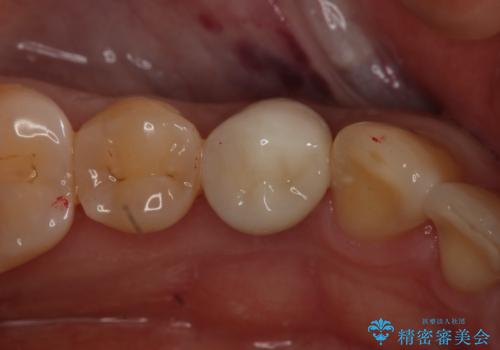

形態、切削量などを考慮し、セラミックインレーにて治療を行いました。

- 154000円(2本分)費用は治療当時の料金となります

メタルインレー、う蝕除去後にCRにて裏層した上で、形成・印象を行いました。